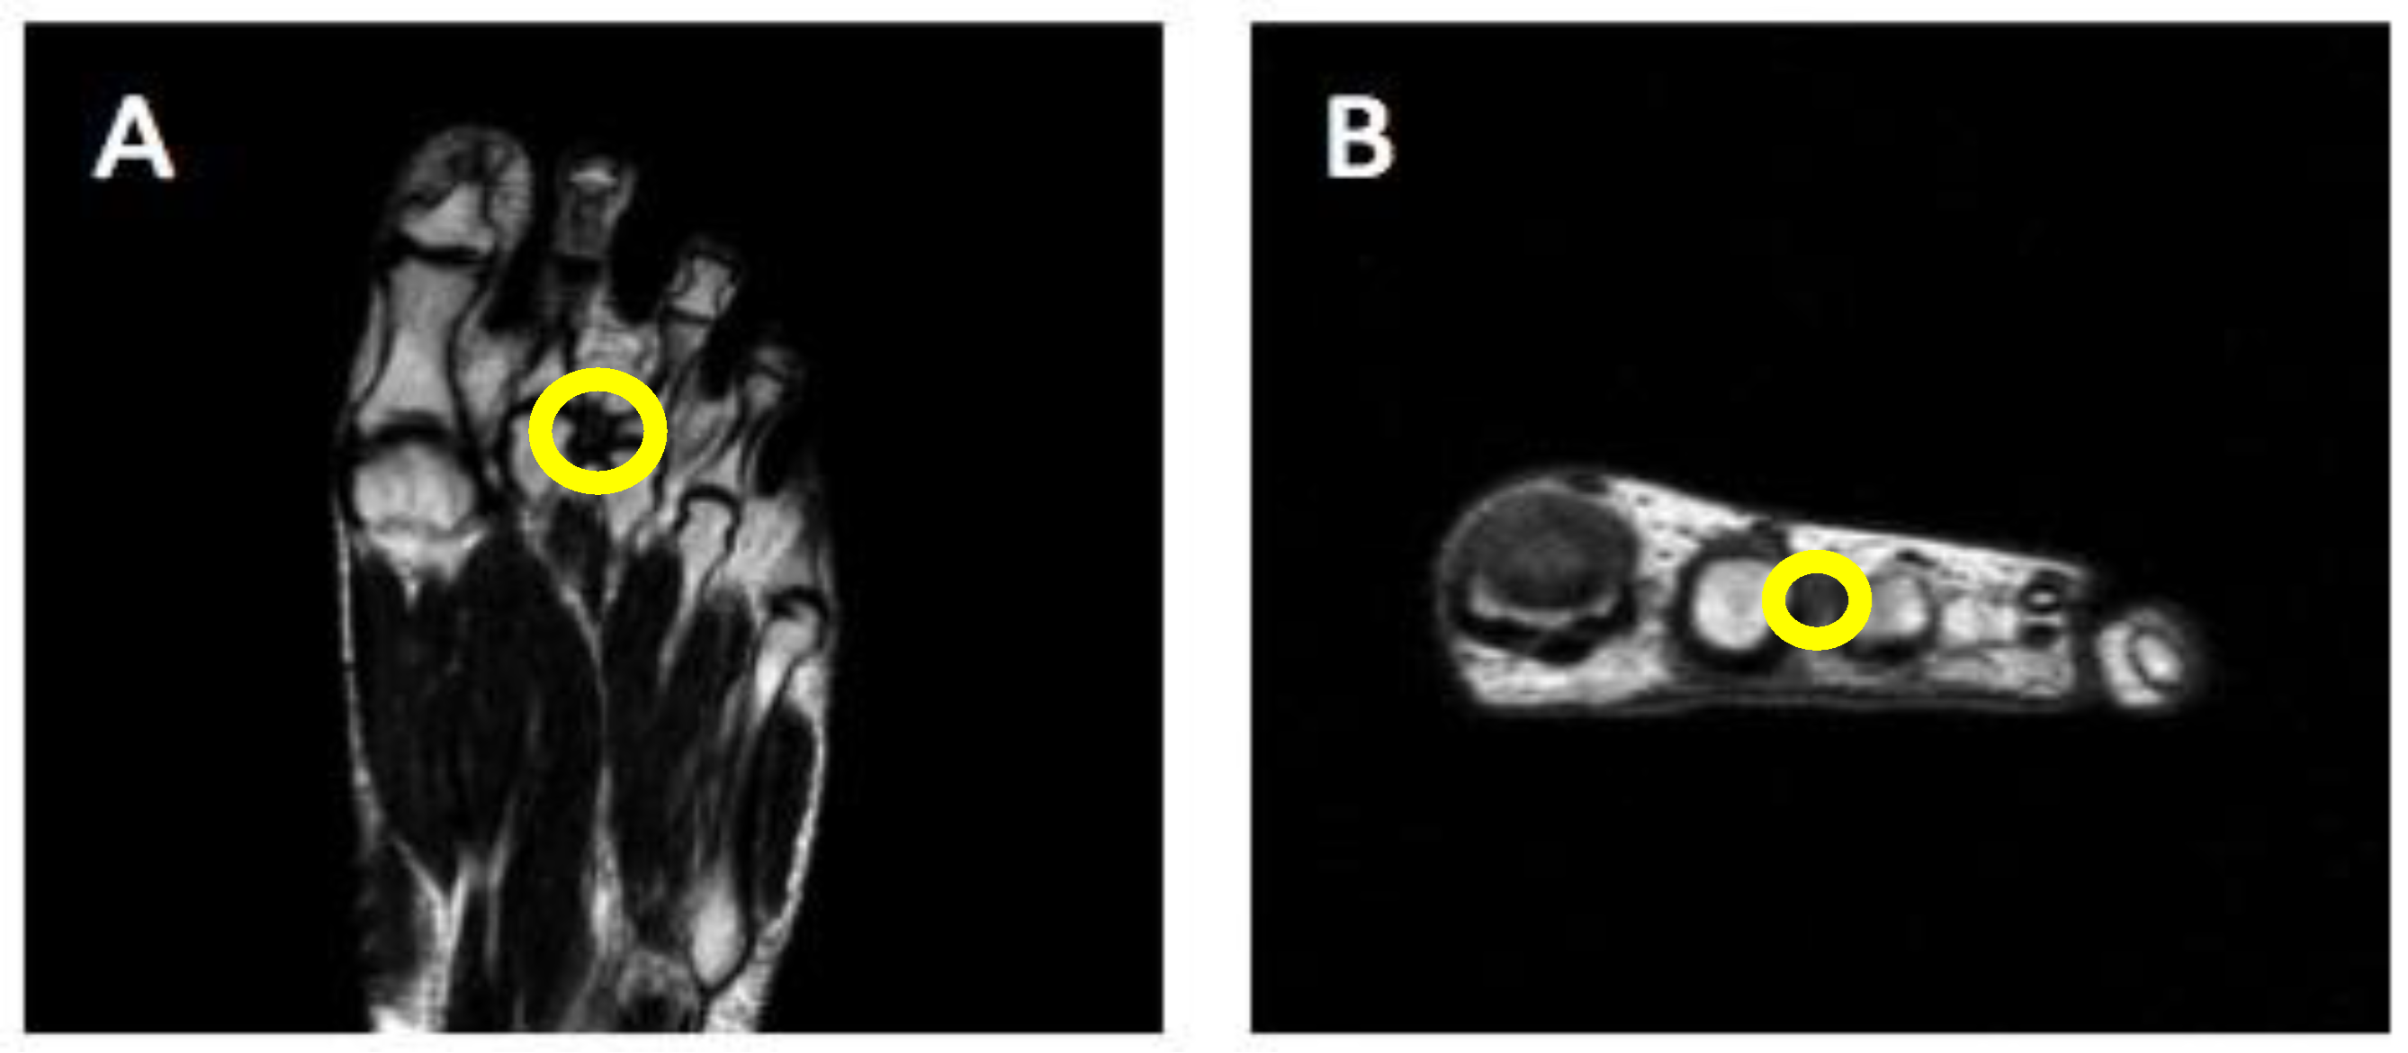

| MN_001 | MRI/US | SIS | <10 mm |

| MN_003 | MRI/US | SIS | <10 mm |